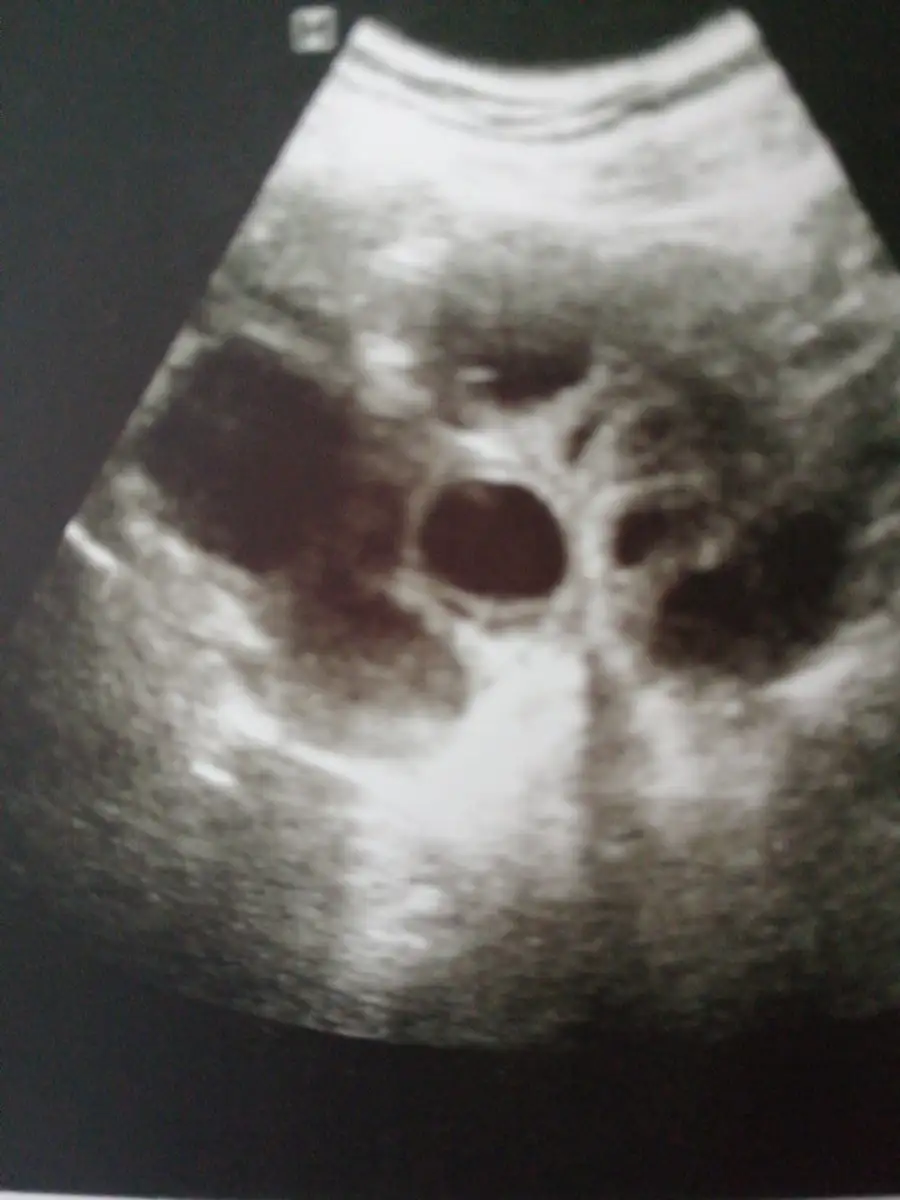

Maşallah seninde mi ikiz canım? Ben fitil ve kan sulandirici igneyi 13. Haftaya kadar kullanacakmisim. Ben keseleri gördüm inşallah kısmetse persembede kalp atislari için randevum var. Sen duydun mu kalp atislarini?Benim transferden beri yapiliyor canim. 4 gunde birdi doktorum kontrolde bebisleri gorunce haftada 1 vurdur dedi.

Allah razi olsun canim evet ikizlermis. Kalp atislarini duymadik dinletmedi ama ayrintili sekilde gosterdi. Burasi kalbi kesesi bebek falan diye anlatti. Gordum yaa bu bana yetti ikisininde minicik kipir kipir atiyodu cok sukur. Ilk basta tutarsa ilaclara ilk 3 ay devam demisti ama kan sulandiricilari kesti. Benimde haftaya randevum yine gel demisti testler yapilacakmis. Senin ki de mi ikiz keseler demissin canimMaşallah seninde mi ikiz canım? Ben fitil ve kan sulandirici igneyi 13. Haftaya kadar kullanacakmisim. Ben keseleri gördüm inşallah kısmetse persembede kalp atislari için randevum var. Sen duydun mu kalp atislarini?